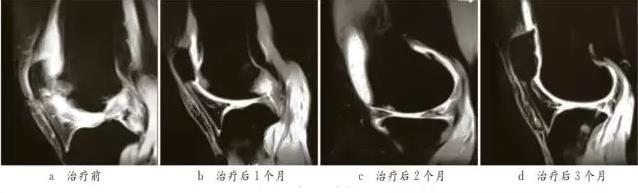

2017年有醫(yī)院采用從患者腹部脂肪中提取分離出間充質(zhì)干細(xì)胞,復(fù)合玻璃酸鈉、自體富含血小板的血漿,對(duì)骨性關(guān)節(jié)炎患者進(jìn)行關(guān)節(jié)腔內(nèi)注射進(jìn)行治療。此后經(jīng)過幾個(gè)月的數(shù)據(jù)監(jiān)測(cè),接受干細(xì)胞治療的骨性關(guān)節(jié)炎患者沒有不良反應(yīng),膝蓋的疼痛也大幅度緩解,同時(shí)活動(dòng)也更加靈活,生活質(zhì)量明顯提升。

MRI掃描顯示,治療后關(guān)節(jié)面斑片狀影顯著減少,軟骨厚度增加

同時(shí),在2017年眾多骨科醫(yī)院及風(fēng)濕醫(yī)院或者機(jī)構(gòu)均做了大量的臨床試驗(yàn),并隨訪了1年左右,結(jié)果顯示:間充質(zhì)干細(xì)胞能更快速、更顯著、更持久的減輕患者關(guān)節(jié)疼痛,改善關(guān)節(jié)的功能。同時(shí)也得出數(shù)據(jù):干細(xì)胞治療骨性關(guān)節(jié)炎注射4次的效果要明顯優(yōu)于2次注射的效果。但遠(yuǎn)期的效果還有待觀察,不過間充質(zhì)干細(xì)胞治療骨性關(guān)節(jié)炎已經(jīng)顯示出了充分的治療潛力,目前還沒有廣泛的運(yùn)用到臨床上,僅在科研所內(nèi)部用于科研可以接受這一療法。但真正全面推廣開來也不會(huì)太久。